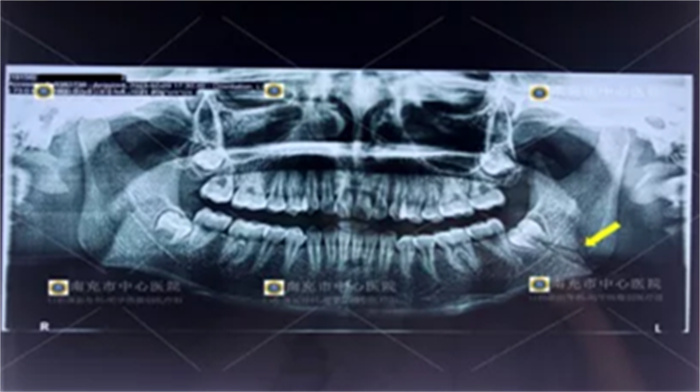

![]() |

| 手术后X片 |

手术当日,由明华伟副主任医师主刀,在科室副主任张兴安主任医师和贾佳欣医师的协助下,手术非常成功,小颜的咬合、面型、张口功能都得到了完全恢复,也没有任何神经损伤等并发症,现已出院。